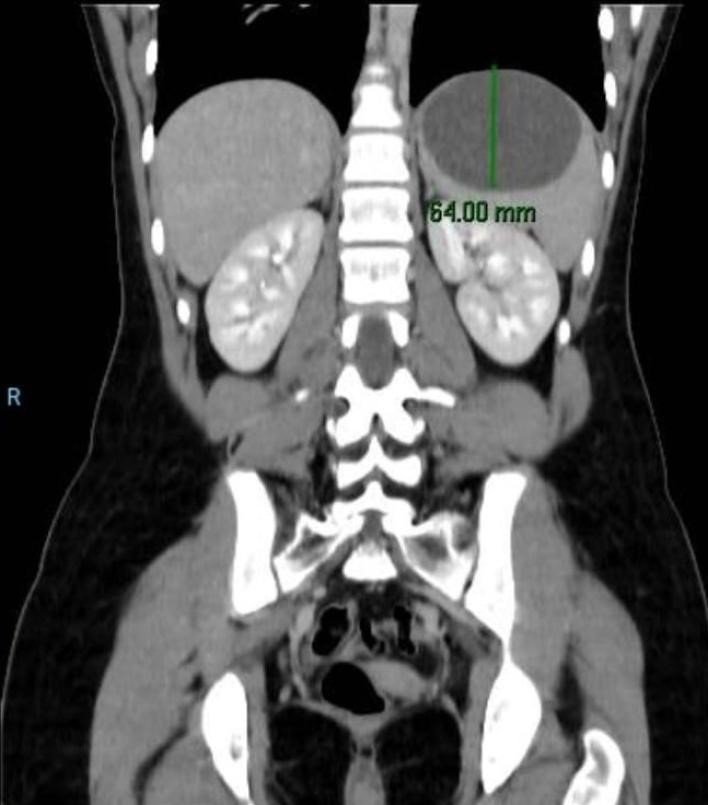

En guardia fue evaluada por el Servicio de Cirugía General Pediátrica. Al momento de la consulta el abdomen era blando, depresible e indoloro. No sé palpaban organomegalias. Se solicitó tomografía computarizada que informaba la presencia de un quiste esplénico de 80 x 70 mm (Figura 1 y Figura 2) y laboratorio para Hidatidosis (IFI – inmunofluorescencia indirecta).

Figura 1: Tomografía Computarizada diagnóstica. Corte corona